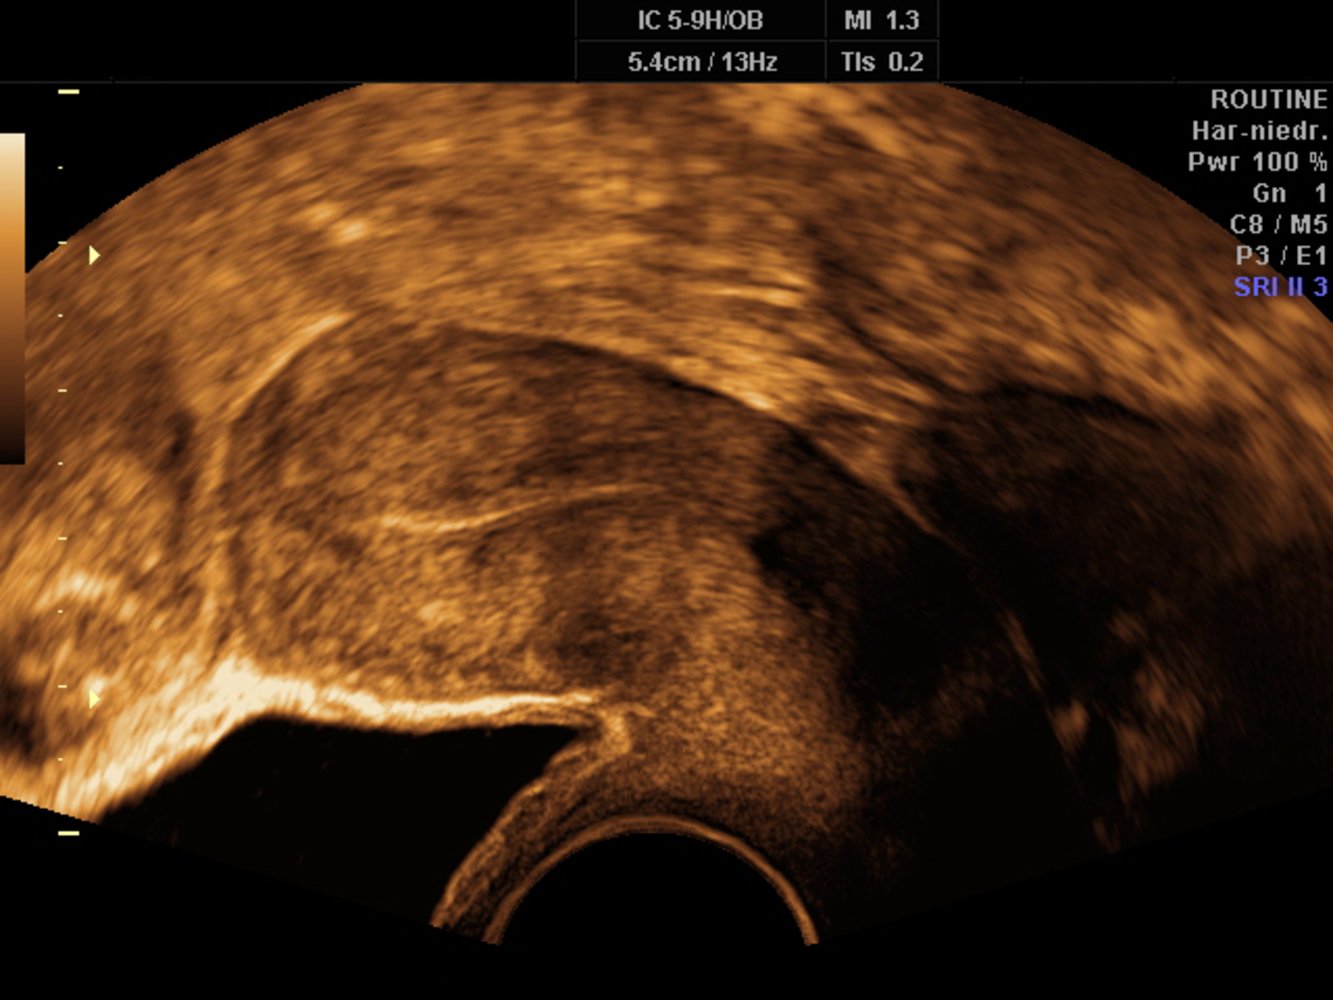

Transvaginal ultrasound

• Ovaries: Performed to diagnose ovarian cysts, tumors, and follicular maturation

• Uterus

• Myometrium (e.g., to diagnose leiomyomas)

• Endometrium

• Echogenic layer in the long axis view of the uterus (referred to as the ā€œendometrial stripeā€)

• Endometrial thickness varies with the menstrual cycle

• Postmenopausal women with an endometrial thickness greater than 8 mm should undergo a follow-up ultrasound after 1–3 months

• Postmenopausal women with an endometrial thickness greater than 10 mm should undergo hysteroscopy and endometrial curettage to rule out endometrial carcinoma.

• Assessment of fetal development during the first trimester

• Measurement of cervical length in cases of cervical incompetence